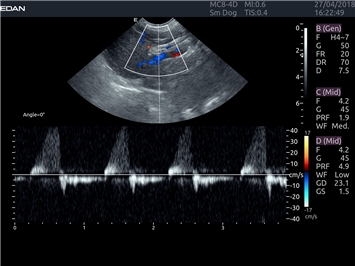

Импульсно-волновой допплер:

Да

Триплексное сканирование:

Дуплексное сканирование: